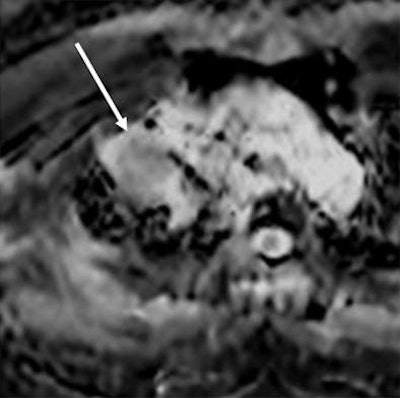

| MR images of a 75-year-old woman with lung cancer who achieved a partial response after two rounds of chemotherapy. ADC maps obtained before (above) and after (below) one course of treatment indicate that the ADC value of the lesion (arrow) increased from 0.99 to 1.48 x 10-3 mm2/sec after therapy. Images courtesy of Radiology. |